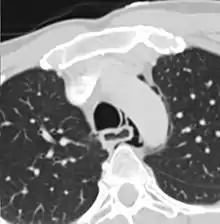

The diagnosis of Boerhaave's syndrome is suggested on the plain chest radiography and confirmed by chest CT scan. The initial plain chest radiograph is almost always abnormal in patients with Boerhaave's syndrome and usually reveals mediastinal or free peritoneal air as the initial radiologic manifestation. With cervical esophageal perforations, plain films of the neck show air in the soft tissues of the prevertebral space.

Hours to days later, pleural effusion(s) with or without pneumothorax, widened mediastinum, and subcutaneous emphysema is typically seen. CT scan may show esophageal wall edema and thickening, extraesophageal air, periesophageal fluid with or without gas bubbles, mediastinal widening, and air and fluid in the pleural spaces, retroperitoneum or lesser sac.